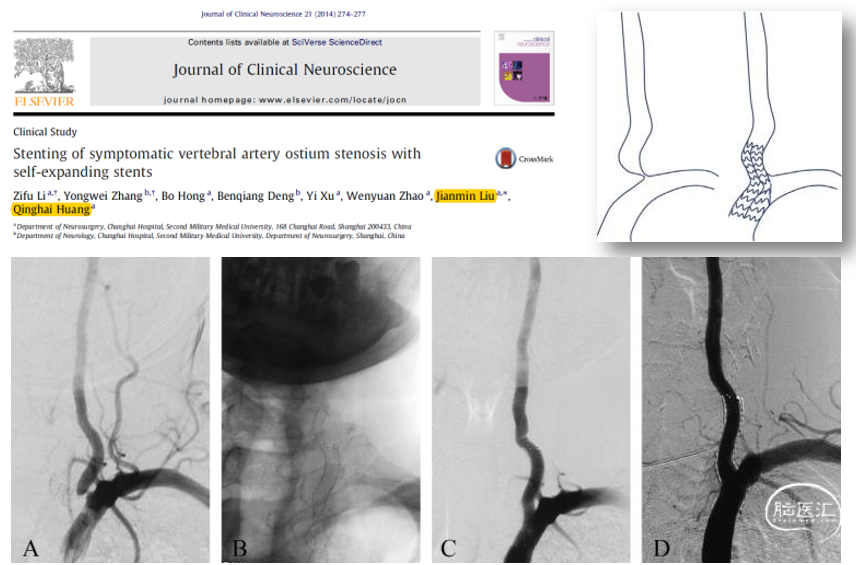

自膨胀支架

Journal of Clinical Neuroscience 21 (2014) 274–277

颈动脉支架

· VA直径>4.5mm

· SCA直径<10mm

随访3-34M

· 再狭窄率 3.1%

· 断裂率 0%

· 30天内无后循环缺血并发症